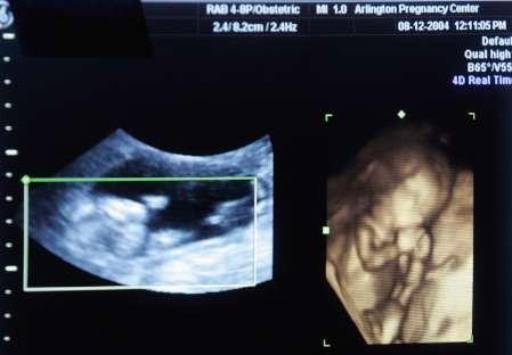

Kantabai Gunvant Thakre, la sessantenne donna di origine indiana protagonista di questa incredibile storia, aveva cominciato a lamentare dei dolori allo stomaco da circa 2 mesi e, successivamente, gli ultrasuoni avevano rivelato una massa che sembrava cancerogena.

L’ecografia però ha stabilito che non si trattava di un tumore, ma di una massa calcificata. Grazie alla risonanza magnetica sono emersi anche organi appartenenti a questo corpo estraneo.

La dottoressa Murtaza Akhtar, a capo del reparto di chirurgia del Lata Mangeshkar Hospital, ha commentato: “è stato dopo che la donna è stata sottoposta a una risonanza magnetica che i medici hanno potuto constatare che si trattava dello scheletro di un bambino”.

Nel caso della donna indiana un team di medici ha eseguito una delicata operazione per rimuovere il feto calcificato che si era stabilito tra l’intestino, la vescica e l’utero.

Alla fine è stato rinvenuto un feto completo di tutte le ossa.